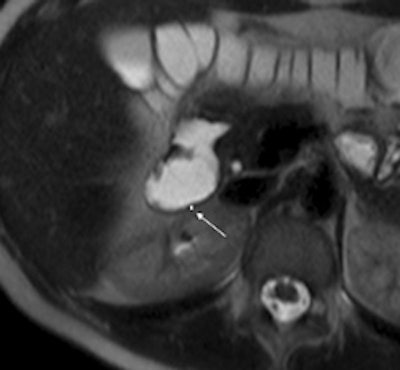

| 1.5-tesla MR images show a portion of the duodenum wall in a patient with untreated celiac disease (above), a patient with treated celiac disease (below), and a healthy patient (bottom). The images show no significant differences in duodenal wall thickness (arrow). |

Their analysis found that a mean maximum enhancement of the duodenal wall was 229.1 ± 46.4 in untreated patients with celiac disease, 109.8 ± 27.8 in treated patients with celiac disease, and 94.7 ± 17.9 in control subjects.

"This MR parameter was significantly higher in patients with untreated celiac disease than in patients with treated celiac disease and control subjects," the authors wrote, while maximum enhancement did not significantly differ between the patients with treated celiac disease and controls.

The researchers also found that duodenal wall thickness did not significantly differ between patients with celiac disease who were not treated for the condition, patients with celiac disease who were treated, and healthy control subjects.